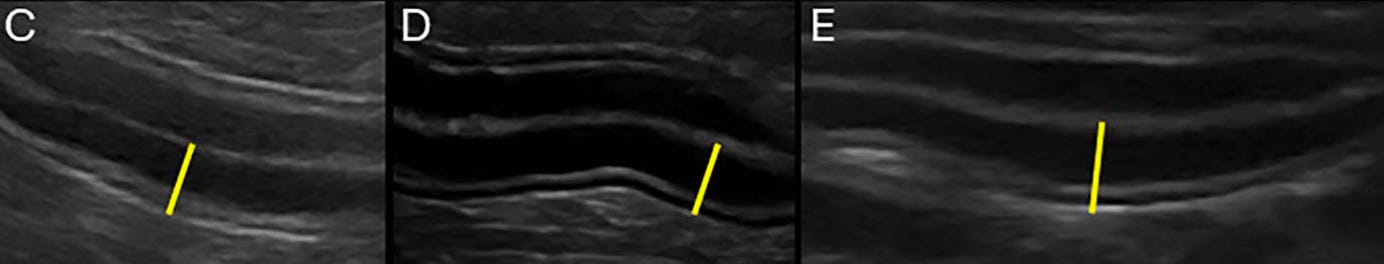

Diferentes grados de engrosamiento de la pared intestinal y la mucosa:

El engrosamiento de la pared intestinal es común en la EIC, pero no es predictivo de inflamación.

Los cambios en la ecogenicidad mucosa, la corrugación del ID y una puntuación ecográfica acumulada elevada se asocian con EIC sintomática, pero no con la gravedad histopatológica.

La mucosa del ID hipoecogénica normal con EIC tiene ≥80% de sensibilidad y especificidad para la EIC-FR, pero los hallazgos se solapan entre los subtipos de EIC.

Los hallazgos secundarios (ej. linfadenopatía, corrugación del ID) pueden ser muy sugestivos de linfoma GI en oposición a EIC.